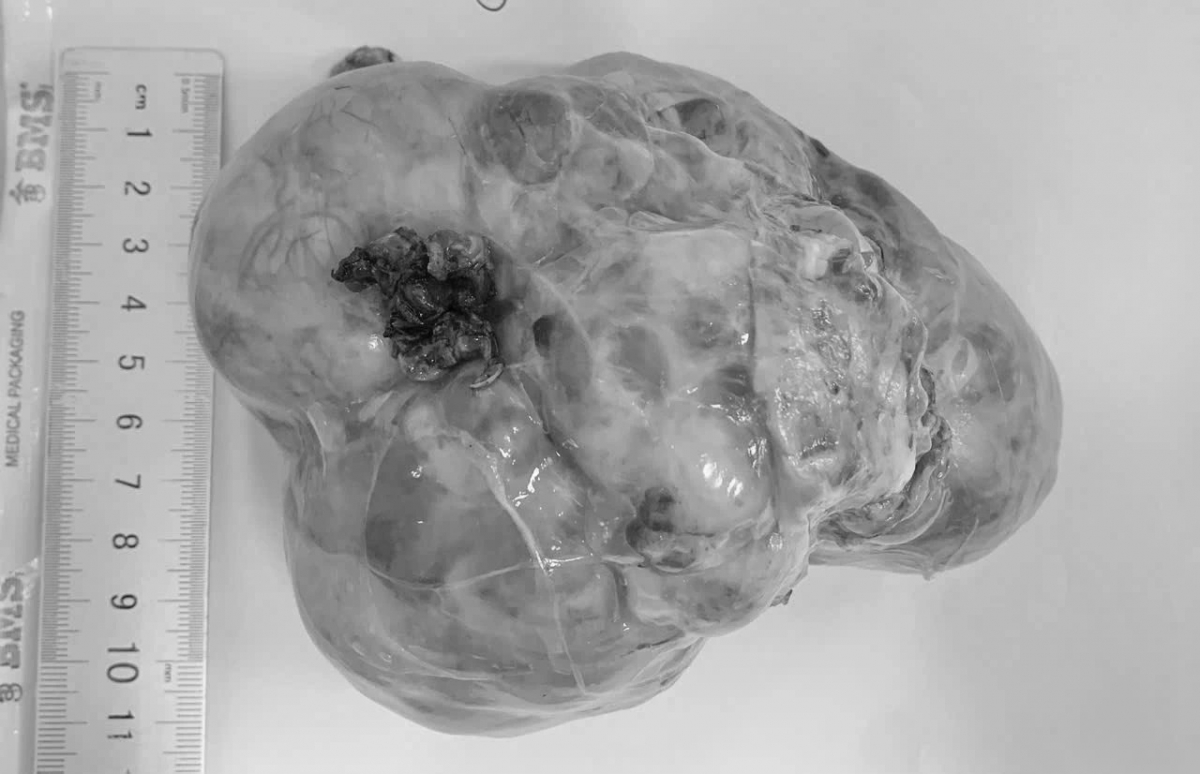

Không chỉ trẻ lớn, bệnh lý này cũng có thể xảy ra ở trẻ sơ sinh và trẻ nhỏ. Tại Bệnh viện Sản – Nhi Đà Nẵng, một bé mới hơn 4 tháng tuổi được phát hiện khối u trong ổ bụng sau khi gia đình thấy bụng bé to bất thường. Khi kiểm tra, khối u đã có kích thước khoảng 15cm, khiến gia đình vô cùng hoảng hốt bởi trước đó trẻ vẫn ăn ngủ bình thường.

“Có trường hợp khối u xuất phát từ thận nhưng đã phát triển rất lớn, chiếm gần toàn bộ quả thận. Trong quá trình phẫu thuật, chúng tôi buộc phải cắt bỏ cả quả thận để loại bỏ khối u. Điều này không chỉ khiến ca mổ phức tạp hơn mà còn tiềm ẩn nhiều nguy cơ đối với sức khỏe của trẻ”- bác sĩ Phong cho biết.